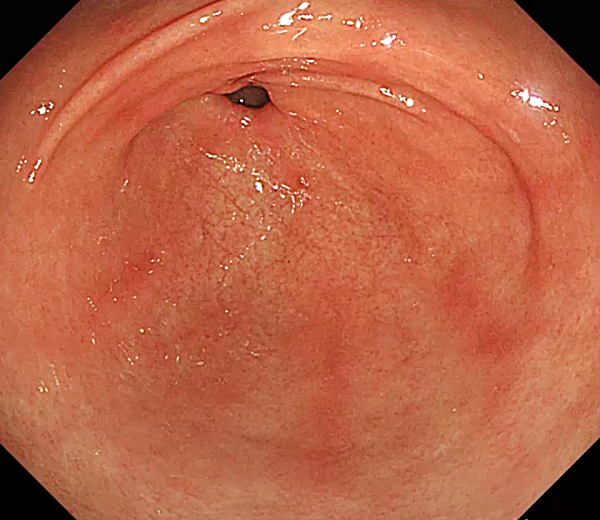

담즙 역류성 위염

- 십이지장의 담즙이 위로 역류하여 위 점막에 염증을 일으키는 질환입니다.

- 위 절제 수술, 십이지장 궤양, 담낭 질환 등으로 인해 발생할 수 있습니다.

- 속 쓰림, 구토, 복통, 식욕 부진 등의 증상이 나타날 수 있으며, 위액에 노란색 담즙이 섞여 나올 수 있습니다.

- 담즙 역류를 억제하는 약물, 위산 분비 억제제, 점막 보호제 등을 사용하여 치료합니다.